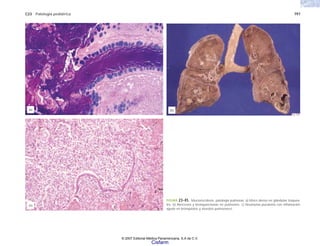

Por hipoperfusión:

hipotrofia

infarto